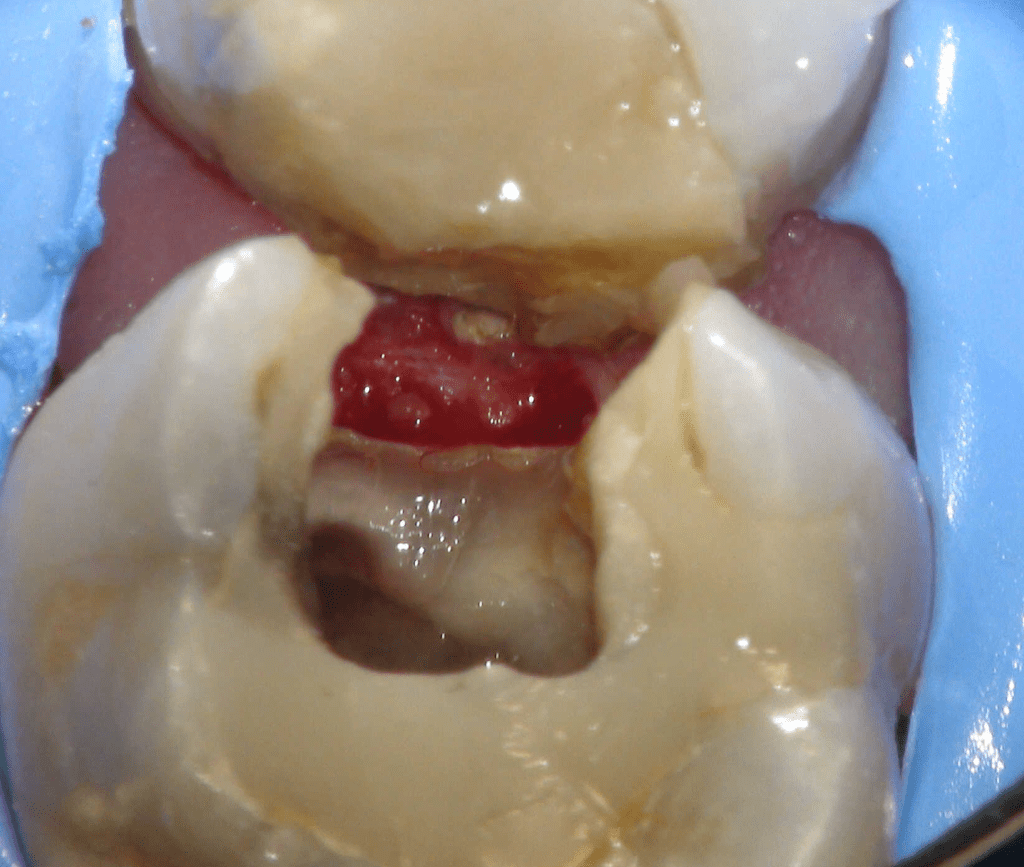

Pulpotomía biodentine + reco preendio